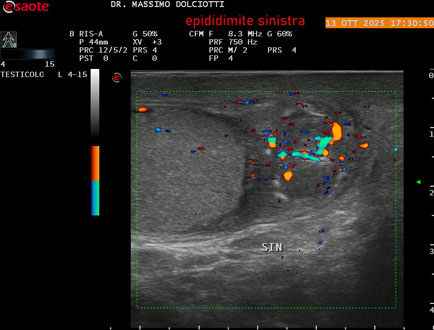

Data inserimento: 12/06/2024

Ecografia del: 14/05/2024

Strumento: Esaote MyLab Eight

Sonda: Lineare Multifrequenza 4-15 MHz

Età Paziente: M 73 anni

Motivazione dell'esame: da 7 gg dolore e tumefazione scrotale.

Commento all'esame: le immagini ed il video documentano, a livello scrotale, un modesto incremento di volume del didimo sinistro e dell'epididimo sinistro, con incremento di vascolarizzazione come da flogosi, da ricondurre ad orchiepididimite, modesto idrocele sinistro.

Conclusioni: orchiepididimite sinistra (left epididymis orchitis).

Presentazione: Dr. Massimo Dolciotti - Ancona